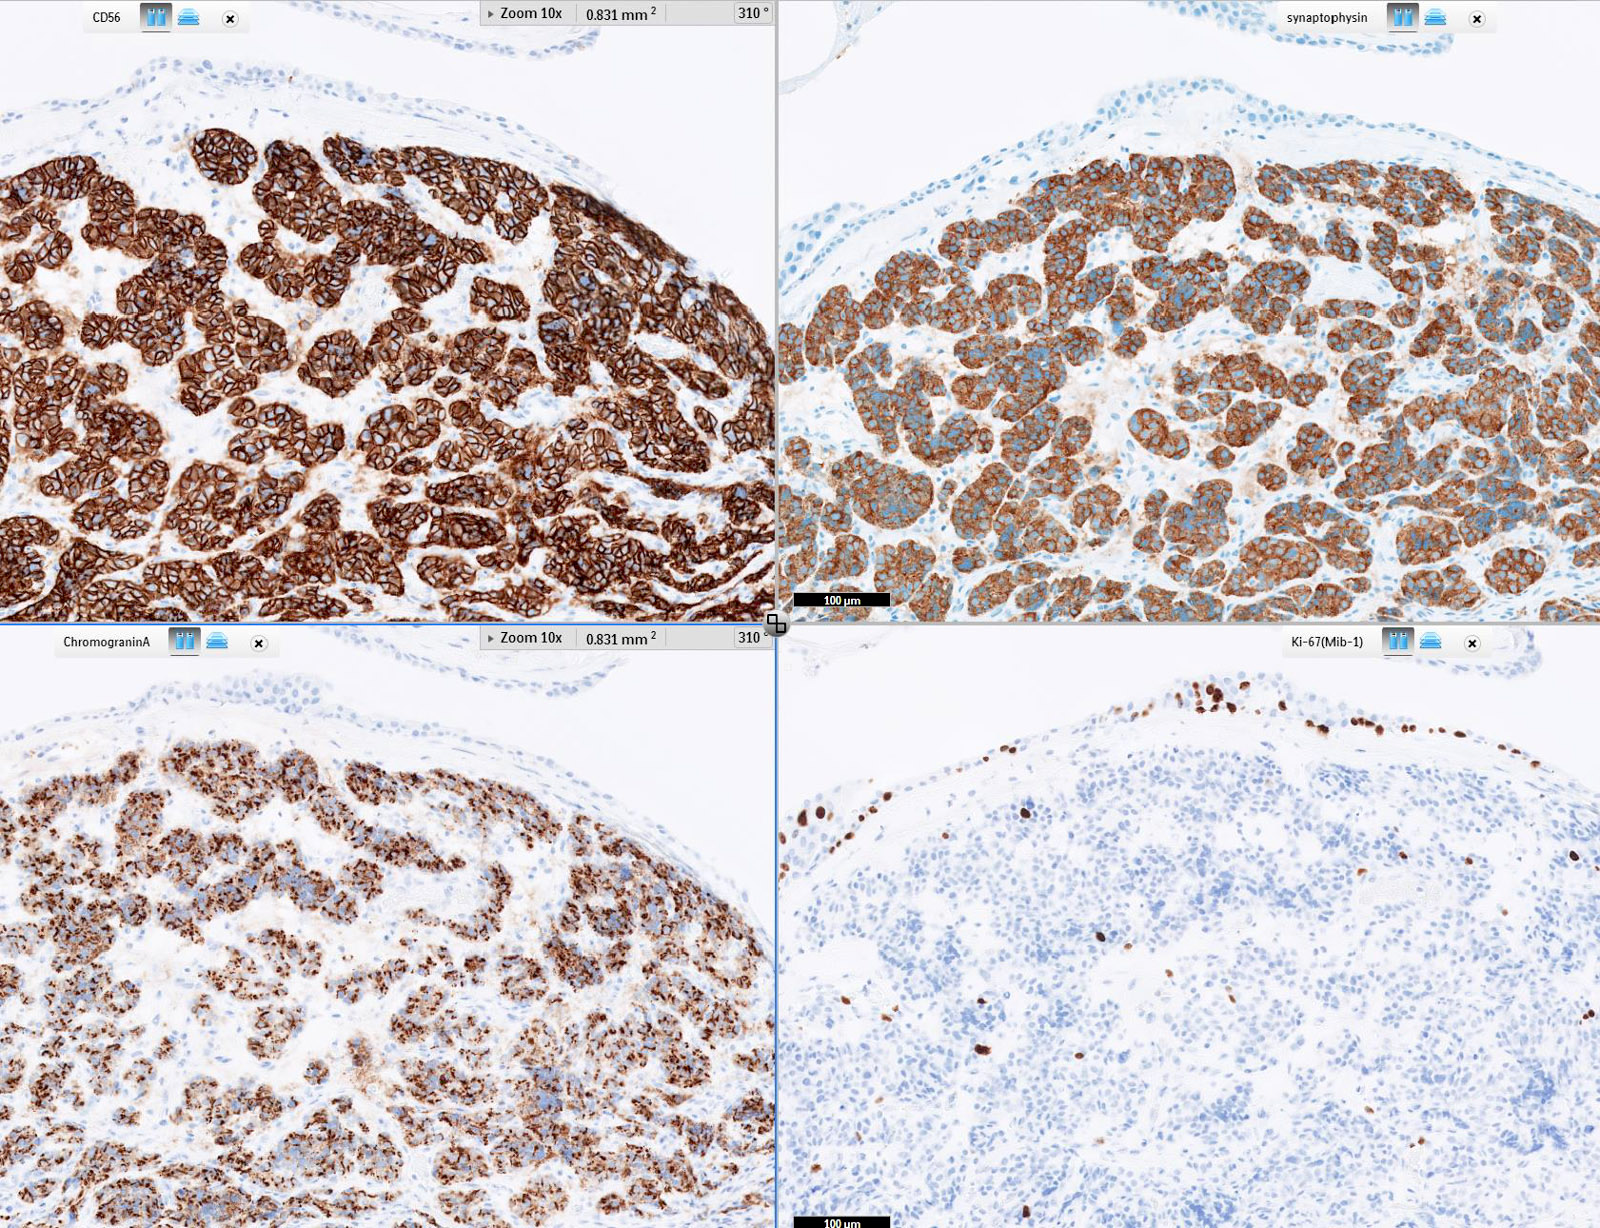

Contributed by Philippe Joubert, M.D., Ph.D., Jijgee Munkhdelger, M.D., Ph.D. and Andrey Bychkov, M.D., Ph.D.

- Chromogranin, synaptophysin, CD56 and INSM1: diffusely and strongly positive (Mod Pathol 2019;32:100)

- Pancytokeratins: positive, useful to distinguish from paraganglioma (Arch Pathol Lab Med 2010;134:1628)

- Ki67 (expected < 20%)

- Ki67 proliferative index does not have an impact on tumor classification; WHO classification states that is desirable to routinely report its value

- Mostly useful to discriminate between high grade neuroendocrine tumors (small cell carcinoma and large cell neuroendocrine carcinoma), on small or crushed biopsies in particular (Arch Pathol Lab Med 2018;142:947)

- Utility of differentiation between typical and atypical carcinoid is not proven (Virchows Arch 2017;470:153)

- TTF1: useful marker of pulmonary lineage in typical and atypical carcinoids but only positive in < 50% of cases

- TTF1+ carcinoids are more commonly seen in peripheral lesions and staining is commonly focal and weak (Hum Pathol 2004;35:825)

- Rb: preserved in the vast majority of pulmonary carcinoids (Transl Lung Cancer Res 2017;6:513)